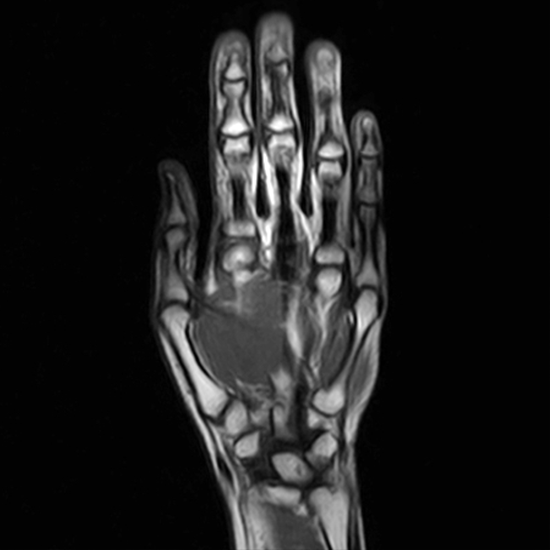

MRI Palm

A magnetic field is used to create images of the palm during a magnetic resonance imaging (MRI) procedure. Aside from any soft tissues, these pictures will also reveal the condition of the bone. Any fluid or edoema are also revealed by this scan, along with ligament and tendon damage. Additionally, it will display the severity of carpal tunnel syndrome and cartilage damage.

Because the articular cartilage and other minor supporting soft tissue components can be seen more clearly.